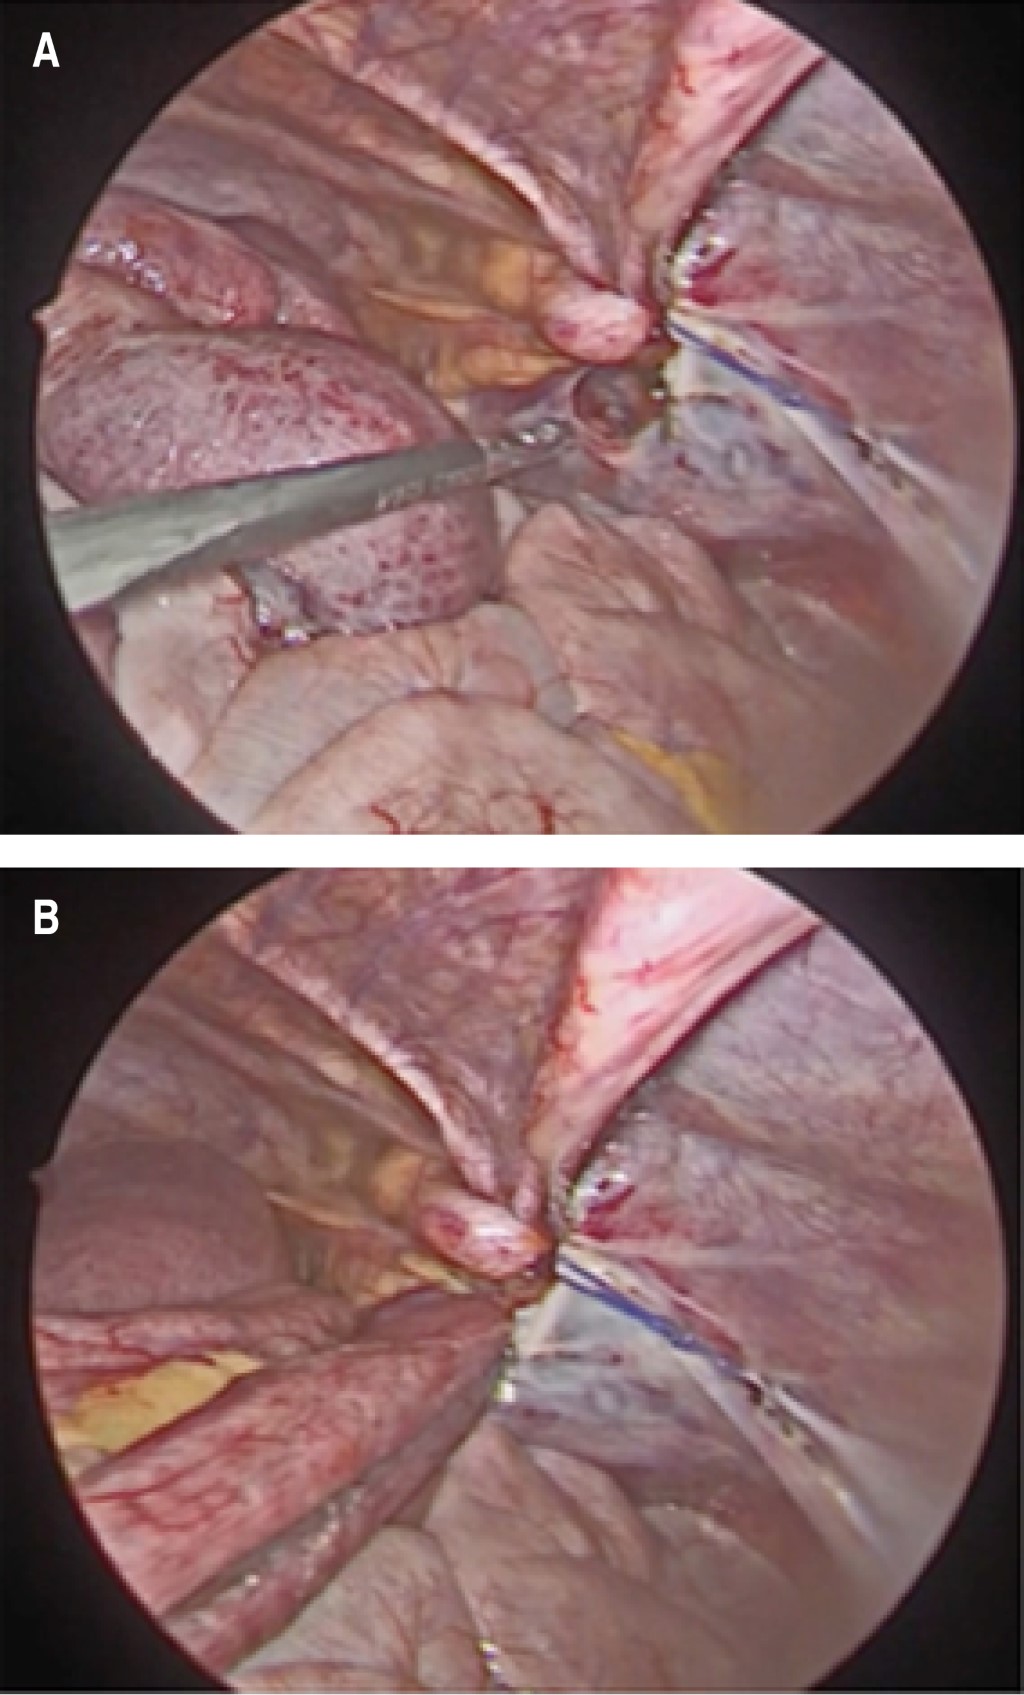

The patient was admitted for observation, intravenous hydration with lactated Ringer's solution was administered, and symptomatic medical management was instituted, persisting with symptomatology, for which the placement of a nasogastric tube (NGT) and a computed tomography (CT) scan of the abdomen with intravenous contrast was indicated. The abdominal CT scan demonstrated a small bowel obstruction with a suspected internal hernia (Figure 1). Based on clinical and radiological findings, it was decided to perform an emergency diagnostic laparoscopy. A small bowel loop herniated into the preperitoneal space through a peritoneal defect was identified as the origin of the obstruction (Figure 2). No evidence of loop distress was identified, so the hernia was reduced, and subsequent closure of the peritoneal defect with polyglactin 910 2-0 cross-stitches was done.

Figure 1